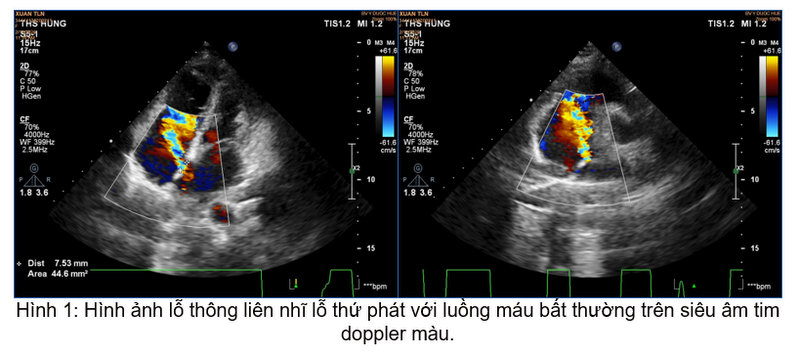

Xác định đây là nguyên nhân gây ra các triệu chứng trên bệnh nhân cũng như khảo sát kỹ cho thấy hình thái cấu trúc, chức năng tim phù hợp, bệnh nhân đã được chỉ định điều trị bằng phương pháp đóng lỗ thông liên nhĩ bằng dù Amplatzer ASD Occluder đường kính 18 mm qua da bằng dụng cụ dưới hướng dẫn của hệ thống tăng sáng số hóa xóa nền và siêu âm tim doppler màu.

Thủ thuật được tiến hành một cách nhanh chóng, an toàn và không xuất hiện biến chứng. Sau thủ thuật, triệu chứng bệnh nhân cải thiện một cách rõ rệt, không còn hồi hộp, khó thở. Kiểm tra lại trên siêu âm tim doppler màu cho thấy lỗ thông liên nhĩ đã được đóng hoàn toàn, không còn dòng chảy bất thường.